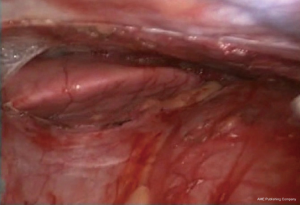

By retracting the thymus toward the right side and the dissection of the thymus is completed anteriorly and posteriorly on the right and upper half of the gland. Now, the left side of the thymus is to be dissected of the pericardium without injuring the left phrenic nerve (Figure 9). To observe the left phrenic nerve, all thymic tissue is pulled toward the surgeon and camera moved anteriorly into the left hemithoracic cavity and the dissection by the phrenic nerve is carried out (Figures 10,11). By completion of the left thymus dissection some of the fatty tissue from left pericardiophrenic angle is dissected.